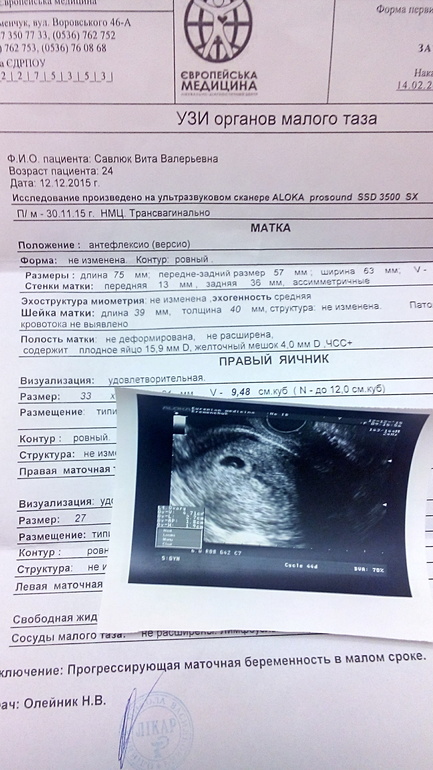

Свд 10 недель

Свд 10 недель 118 фото